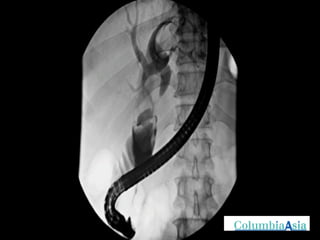

ERCP (Endoscopic Retrograde Cholangio Pancreatography) is an endoscopic procedure used to diagnose and treat issues in the bile and pancreatic ducts. It involves positioning an endoscope and using x-rays to view the ducts while performing procedures like draining bile ducts, removing gallstones, and placing stents. Potential complications include pancreatitis, bleeding, infection, or perforation. Careful pre- and post-procedure steps like monitoring and antibiotics are important to minimize risks.